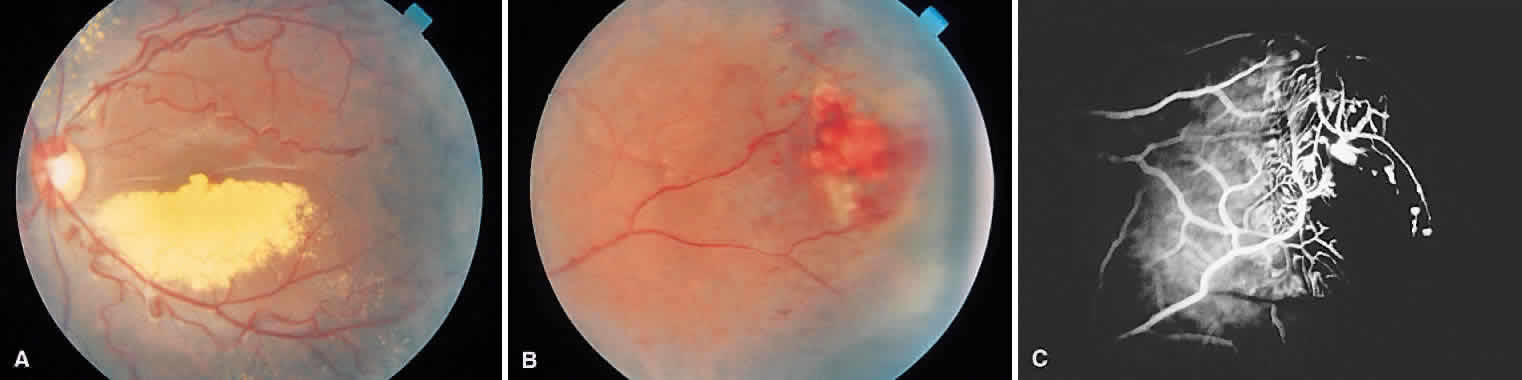

The retinal lesions of angiomatosis retinae are benign vascular anomalies. When the retinal tumor is associated with cerebellar tumors (in approximately 25% of cases), the condition is known as von Hippel-Lindau disease. At a certain stage in the evolution of angiomatosis retinae, the picture is very similar to retinoblastoma (Fig. 9). Both conditions are marked by large feeder vessels that appear to arise de novo in the tumor. When angiomas become gliotic and obscured by overlying detachment, they cannot be clearly differentiated from retinoblastoma. Again, ancillary tests can be useful to detect calcification. When diagnostic difficulty arises and there is no useful vision in the affected eye, the most reasonable course is enucleation.

Fig. 9. A. Capillary hemangioma of the retina with prominent afferent and efferent vessels. B. Fluoroscein angiography showing filling of the tumor with dye. (Courtesy of William Tasman, MD, Philadelphia, PA.)

Coats' disease is a nonhereditary condition found most commonly in males. It is a primary vascular anomaly of the retina characterized by telangiectatic vessels that leak lipoproteinaceous exudate into the retina and subretinal space (Figs. 10 and 11). Later, a detachment with a solid white or yellow-pink material may stimulate a retinoblastoma. Patches of telangiectatic and aneurysmal vessels strongly suggest Coats' disease but are also seen in retinoblastoma. The involved retina often has a characteristic greenish-yellow sheen, and the detached portion of the retina may be dark gray or black as a result of proliferation of the retinal pigment epithelium. Although this can also be a feature of retinoblastoma, it is relatively rare. Cholesterol crystals glistening in the subretinal space strongly suggest a later stage of Coats' disease. Although the vascular anomaly in Coats' disease is probably present at birth, the lesion does not cause symptoms until the retina detaches and central vision is lost, with cases being discovered at an average age of 6 to 8 years.

Fig. 10. A. Coats' disease with exudation in the posterior pole. B. Peripheral retinal telangiectasia responsible for the exudate. C. Fluorescein staining of the peripheral lesion. (Courtesy of William Tasman, MD, Philadelphia, PA.)